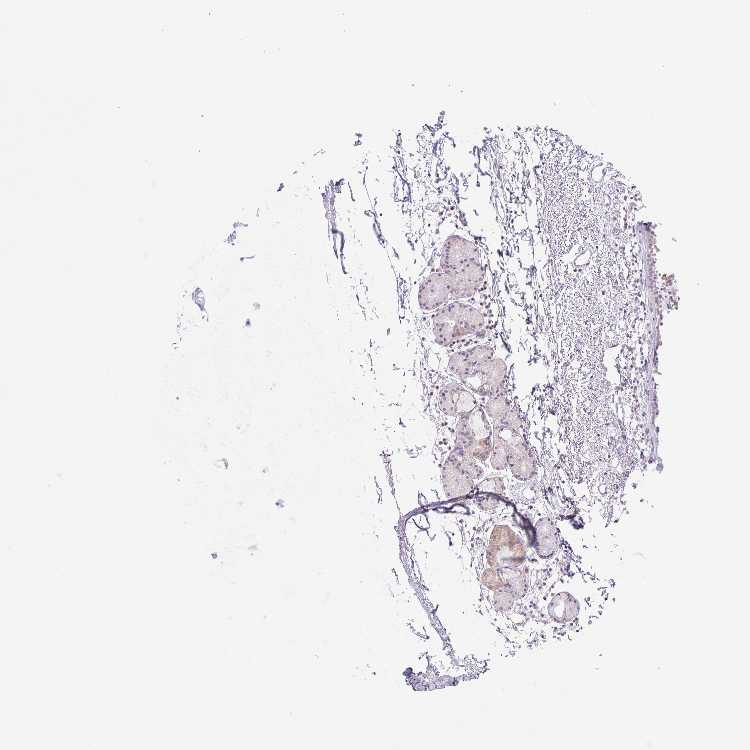

SOFT TISSUE 1 - Antibody stainingi

Antibody staining in the annotated cell types in the current human tissue is reported as not detected, low, medium, or high, based on conventional immunohistochemistry profiling in selected tissues. This score is based on the combination of the staining intensity and fraction of stained cells.

Each image is clickable and will lead to virtual microscopy that enables deeper exploration of all samples and also displays staining intensity scores, fraction scores and subcellular localization as well as patient and tissue information for each sample.

Antibody HPA042953Antibody CAB025860

SOFT TISSUE 2 - Antibody stainingi

Chondrocytes -Low